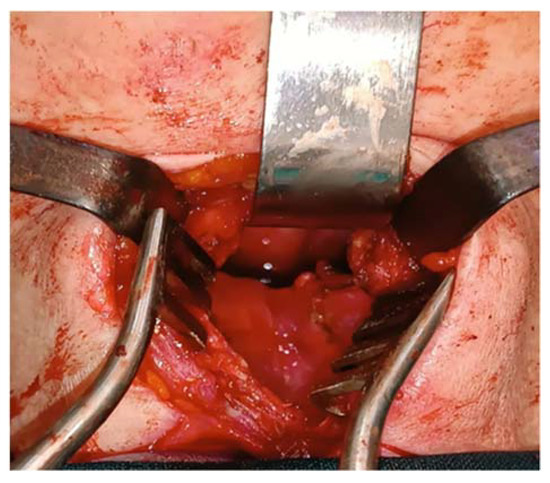

A tumor of 30/30 mm was resected and was sent to the anatomic pathology department (Figure 7). The histological result confirmed the diagnosis of a laryngeal paraganglioma.

Figure 7.

The resected tumor.